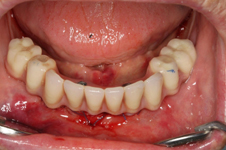

Během let může postupnou ztrátou zubů zůstat v ústech omezený počet zubů, které umožňují držení zubních náhrad.

V důsledku přetížení zbylých zubů např. houpavými pohyb snímacích náhrad dochází k uvolnění těchto zubů a držení můstků a protéz je tak velmi těžké. V těchto případech můžeme pomocí implantátů zvýšit počet pilířů a tím zabránit přetěžování a ztrátě zbylých zubů